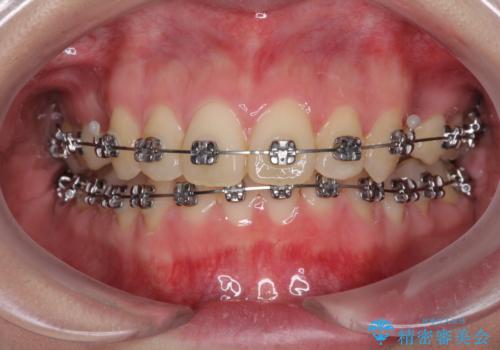

- メタルブラケット

- 治療期間

- 3年1ヶ月